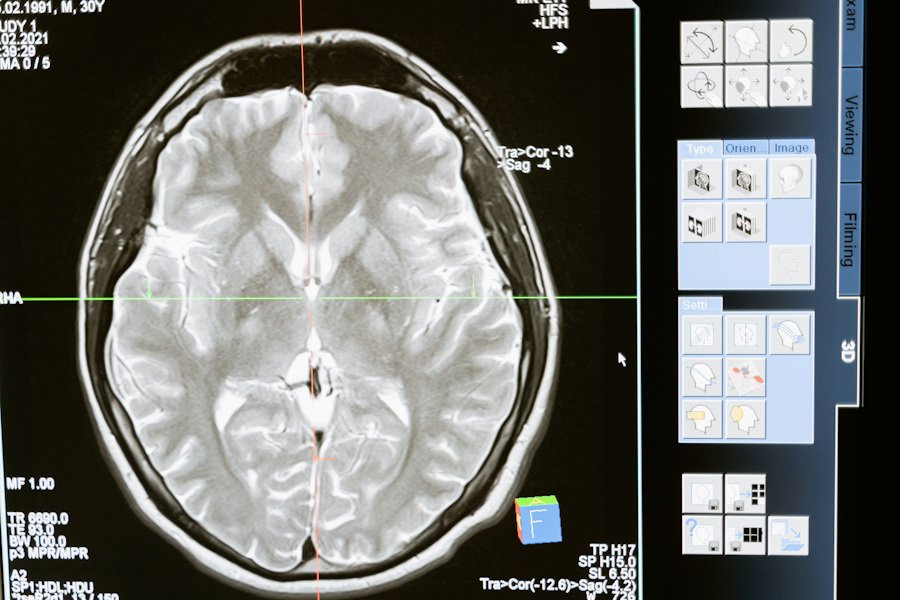

Фото из открытых источников

Ранее ученые использовали функциональную магнитно-резонансную томографию (фМРТ), чтобы определить области мозга, связанные с языковой обработкой. Однако фМРТ, которая измеряет изменения кровотока, не обладает достаточной разрешающей способностью для выявления работы небольших популяций нейронов. Это ограничивало возможность точно определить, какие функции выполняют отдельные группы нейронов.